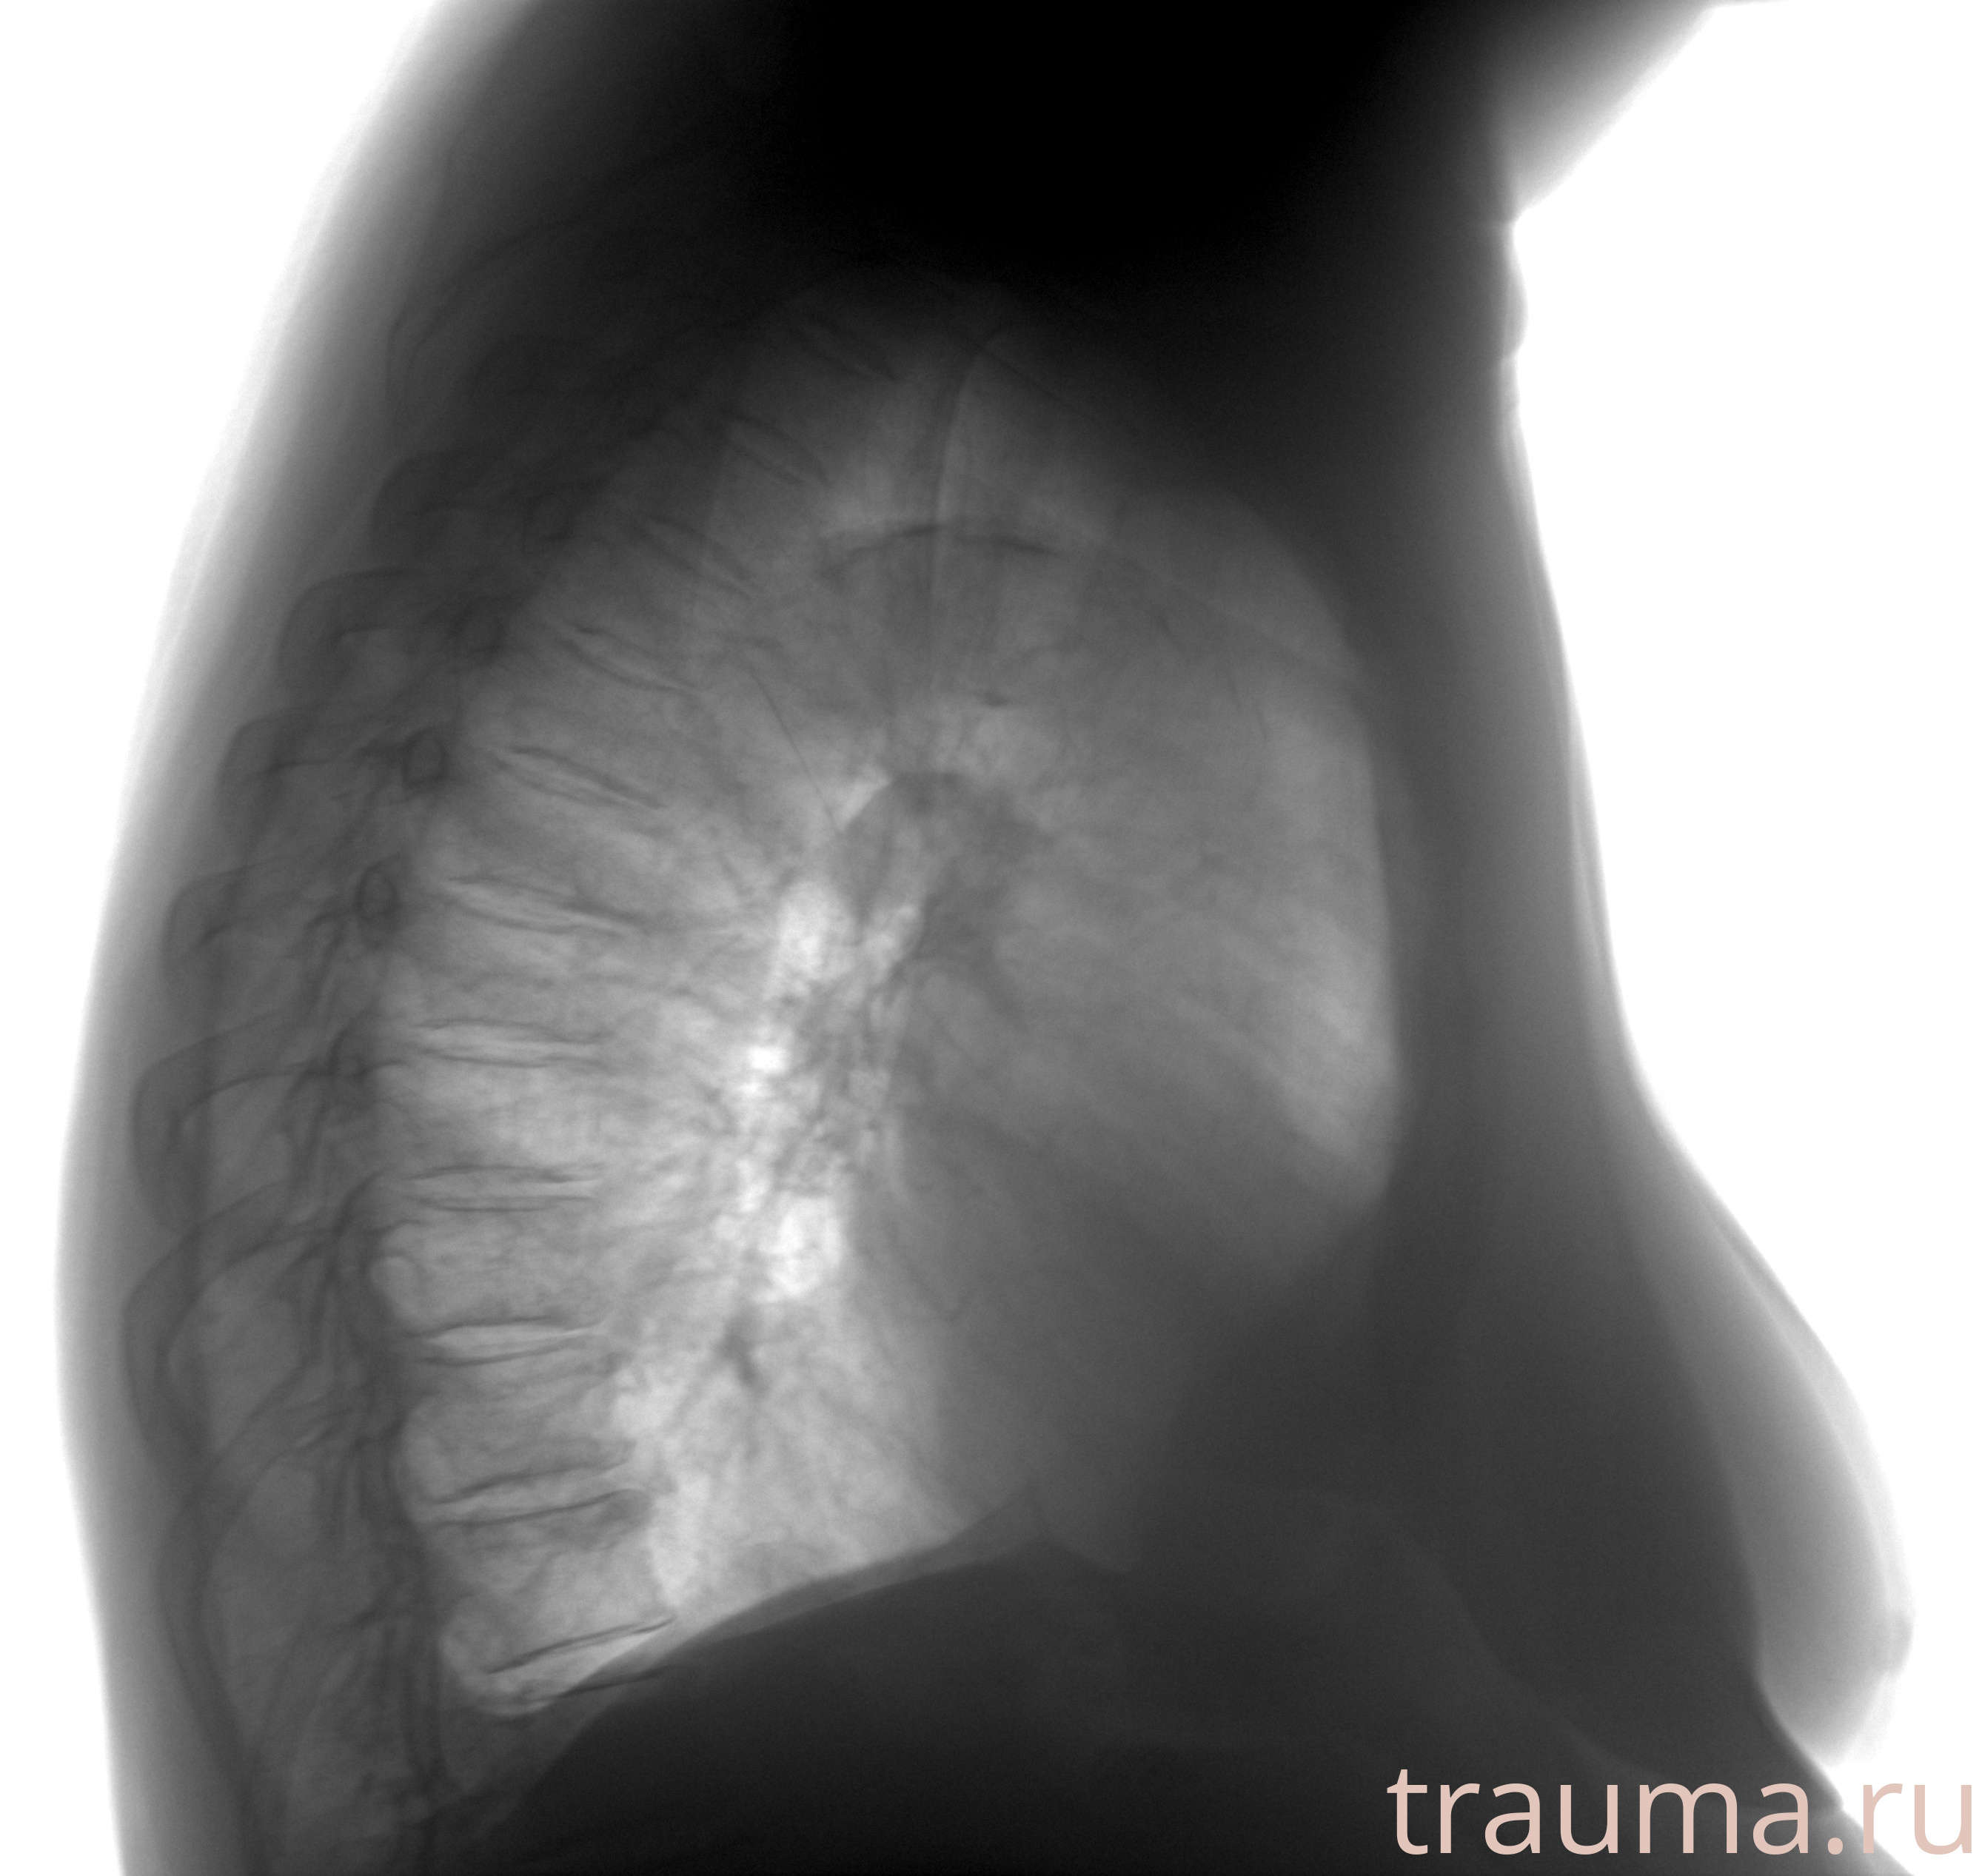

Рентгенограммы

Рентген на дому: по вашему адресу приезжает врач-рентгенолог, травматолог-ортопед с мобильным рентгеновским аппаратом, проводит диагностику травмы или заболевания, делает необходимые рентгенограммы, дает рекомендации по дальнейшему лечению. Получить качественные снимки в домашних условиях возможно благодаря уникальной методике, разработанной МосРентген Центром для института  Склифосовского

при переломе шейки бедра и пневмонии от компании МосРентген Центр - партнера Института имени Склифосовского